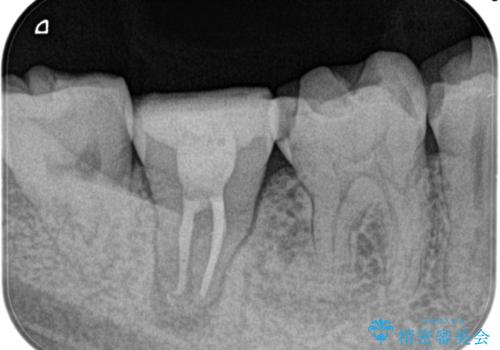

定期検診にて膿の出口を見つけた。精密根管治療

- 定期検診にて膿の出口を見つけたことを主訴に来院されました。

検査の結果、診断を歯髄壊死、症候性根尖性歯周炎とし抜髄を行っております。

- 精密根管治療(イニシャルケース,大臼歯):122,000円、ファイバーコア:22,000円費用は治療当時の料金となります

根管充填はCWCTにて行なっています。